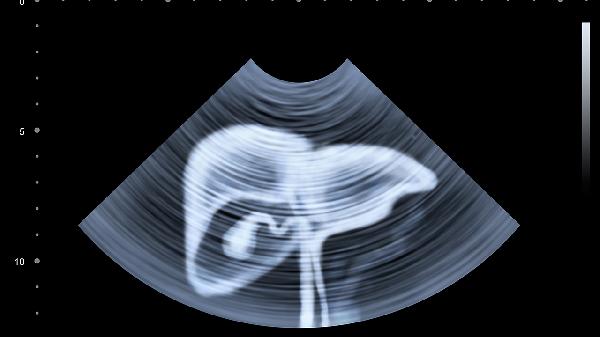

3、膽囊炎:

膽囊炎多由膽囊結(jié)石引發(fā)膽汁淤積所致,疼痛位于右上腹并向右肩放射,可能伴隨發(fā)熱、黃疸。急性發(fā)作需禁食并就醫(yī),慢性期需低脂飲食,必要時行膽囊切除術(shù)。

4、胰腺炎:

胰腺炎常因膽道疾病或酗酒導(dǎo)致胰酶異常激活,疼痛呈持續(xù)性劇痛并向腰背部放射,可能伴隨嘔吐、腹脹。急性胰腺炎屬急重癥需立即住院治療,慢性期需嚴(yán)格戒酒并控制血脂。